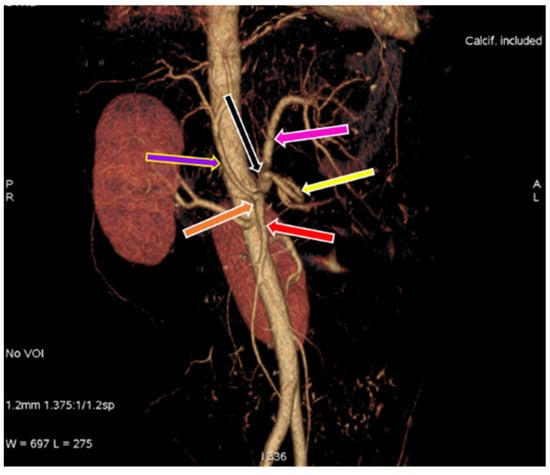

3.1. Variation in Origin and Branching Pattern of Celiac Trunk

3.2. Variation in Origin and Branching Pattern of Hepatic Artery